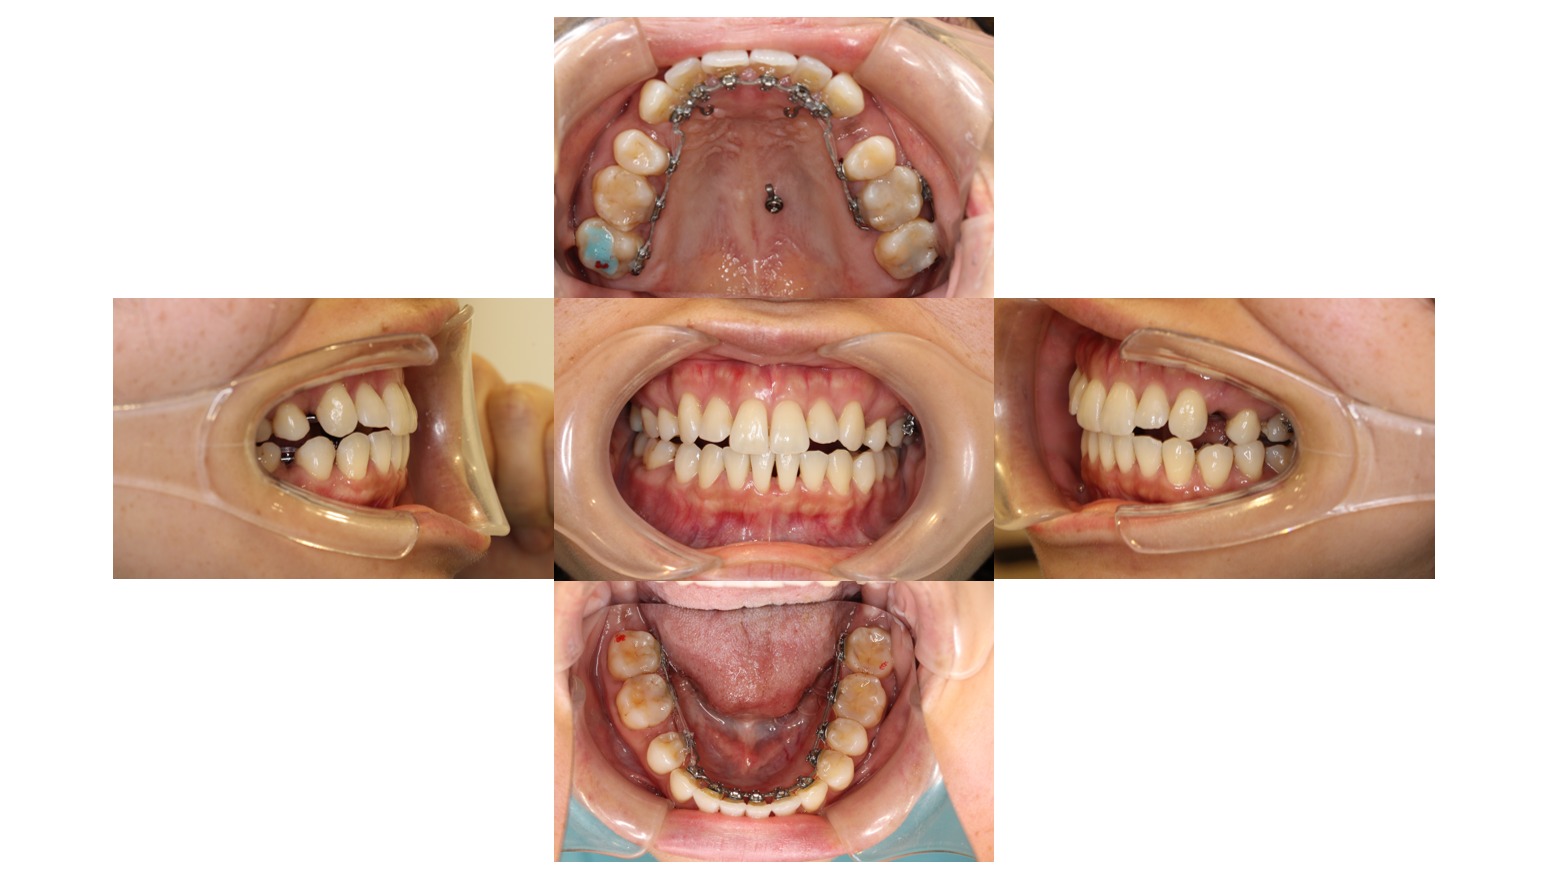

7か月経過

前歯のがたつきが改善したので前歯についていた小さい装置を大きい装置に変えています

1年6か月経過

左側は装置が当たらないのと奥歯で噛めているので青い材料を外しています